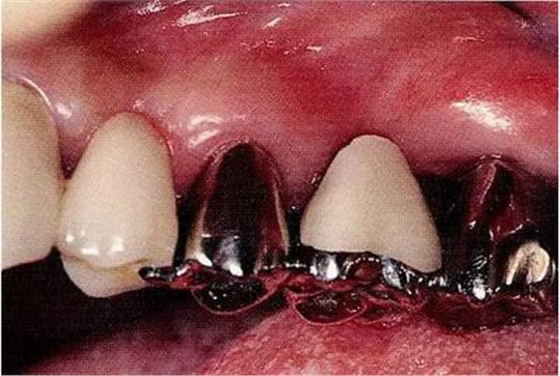

圖16-4進(jìn)行牙齒分割時(shí),如圖所示一樣,要確保分割去除的牙根邊緣不會(huì)殘留在牙槽中間骨脊。如果有邊緣殘留,會(huì)造成軟組織發(fā)紅,引發(fā)炎癥。

▼圖17

圖17將右上6近中頰側(cè)根拔除,考慮到修復(fù)物清潔性的情況下進(jìn)行備牙。牙齒分割后如果有邊緣殘留,就會(huì)使切割面的牙齦發(fā)紅無(wú)法治愈。